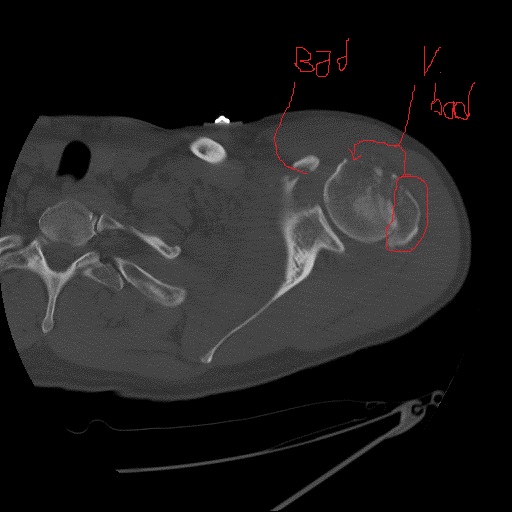

It has been almost three months since my last post here, and things have fallen quiet on our sister blog Anatomy to You, too. I thought it was time for an update, which is mostly a summary of stuff we’ve been doing on my team, but also featuring some interesting images if you stick around. The relative silence here has partly been due to me giving myself some nice holiday time w/family in L.A., then having surgery to fix my right shoulder, then recovering from that and some complications (still underway, but the fact that I am doing this post is itself evidence of recovery).

Stomach-Churning Rating: 4/10; semi-gruesome x-rays of me and hippo bits at the end, but just bones really.

X-ray of my right shoulder from frontal view, unlabelled

Labelled x-ray

Nonetheless, as welfare science likes to term it, it’s entirely “a life worth living”. I have to pick my battles more than I used to, and I’ve had to learn to take more time to get exercise, rest, and avoid the stresses (or even unpleasant people) that can cause my health to take rapid downward spirals. I’m more fragile in many ways, such as having to stop doing karate because my shoulders have weakened. Here’s some interesting anatomy for you from a recent MRI scan of my right shoulder:

My left shoulder in top cross-sectional view, with the missing parts of my humeral head crudely outlined in red. There's more amiss here, too.

My left shoulder in top cross-sectional view, with the missing parts of my humeral head crudely outlined in red. There’s more amiss here, too.

My seizures cause my shoulder flexors to spasm, raising my arms up and crushing my humerus against my glenoid cavity of my scapula and causing occasional dislocations that abrade the humerus against the rim of the glenoid. The result, after numerous seizures, has been the wearing away of the articular cartilage of my shoulder and then the crumbling of the bony head of my humerus. Thus, once my NHS surgeon is ready to in coming months, I am due to have my coracoid process of my scapula cut off and moved, with its attached muscles and ligaments, to be screwed into the front of my glenoid cavity, bracing my humeral head more tightly against the glenoid and thereby resisting future dislocations. Luckily that operation can be done with several small incisions and endoscopy; invasive as the surgery is; thus recovery time won’t be so long.

Latarjet surgery (view of right shoulder joint [glenoid] from front): coracoid process moved posteroventrally. More details (w/videos) here.

It amuses me that all of this intense surgery looming on the horizon doesn’t worry me. I just want it done. I’ve been through a comparable surgery with my left shoulder, involving screwing my greater tuberosity back onto my humerus, so I know what recovery is like, and now that shoulder is doing fine. All that aside, my physical integrity has declined and I feel it every day. I may never return to my karate classes and earn that black belt I was seeking as a life-goal, but time will tell. I am trying to do what I can to remain as strong as I can for as long as I can.